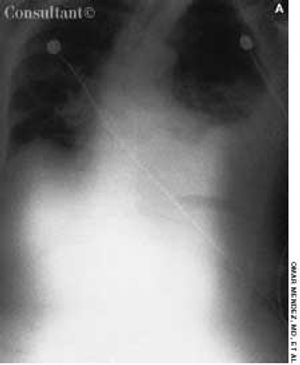

An 85-year-old white woman was brought to the emergency department (ED) with acute, severe left posterolateral chest wall pain of several hours' duration. The nonradiating pain was accompanied by shortness of breath. She denied palpitations, diaphoresis, syncope, or dizziness.